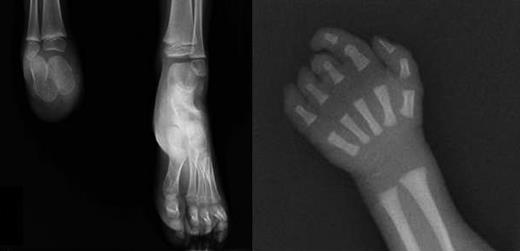

X-rays of limb defects in patients. (Left) Foot x-ray of subject III-1, showing absence of the right foot; the calcaneus and astragalus, that are absent in the father, are present although smaller than the controlateral ones. (Right) X-ray of right hand in subject III-3, showing absence of the last phalange of 2° digit and last 2 phalanges of 3° to 5° digits.

During his wife's first pregnancy, a first-trimester ultrasound scan revealed that the fetus was affected by a skeletal anomaly of the right foot. The mother did not report any substance abuse, did not have gestational diabetes, and underwent chorionic villus sampling at 12 weeks (cytogenetic analysis showed a normal male karyotype). After delivery, it was confirmed that the child (III-1) had a milder lower limb defect, with the upper limbs being spared (Figure 2A). Blood examination showed that the child also has thrombocythemia (> 1000 × 109/L) and TPO concentration was elevated in serum (1385 pg/mL).

The couple had a second child, a boy with normal platelet count and no limb defects (III-2). During the third pregnancy, chorionic villus sampling was performed at 12 weeks of gestation for advanced maternal age and a unilateral foot defect was detected by ultrasound scan at the time. Cytogenetic analysis showed a normal male karyotype. After delivery, a unilateral digital defect was noted (Figure 2B) and the left foot defect was confirmed (III-3). The platelet count was normal at birth, but increased to more than 700 × 109/L 2 months after delivery.